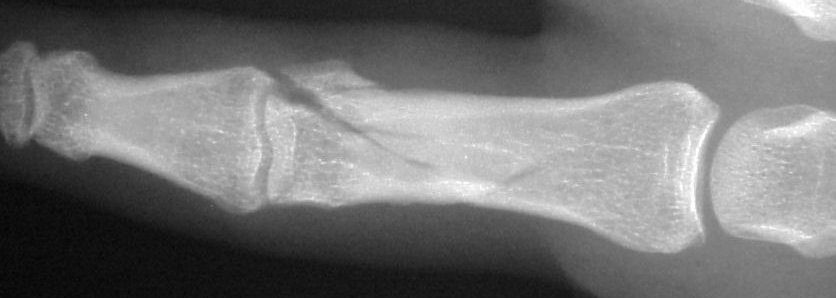

The joint was reconstructed with 1.0mm screws and the shaft fixed with 1.3mm screws using the Synthes titanium modular hand tray.

Six months after surgery: